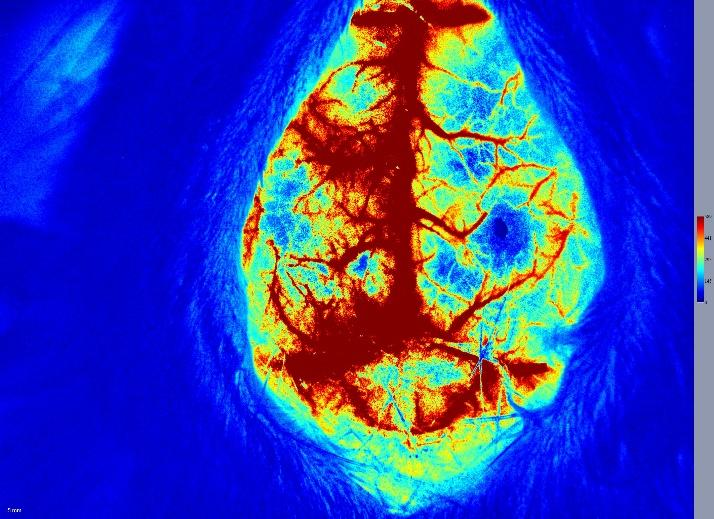

影像学评价:MRI或PET成像,无创评估梗塞范围和代谢变化。